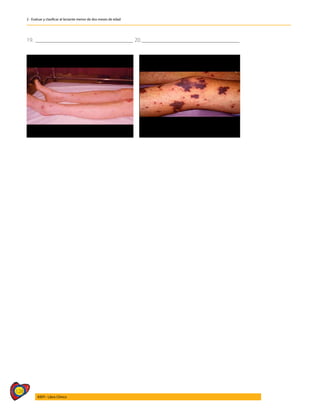

10. VERIFICAR LA POSIBILIDAD DE MALTRATO EN EL NIÑO.....................................................................245

10.1 DEFINICIÓN Y CLASIFICACIÓN DEL MALTRATO INFANTIL..............................................................246

10.1.1 MALTRATO FÍSICO...............................................................................................................................................247